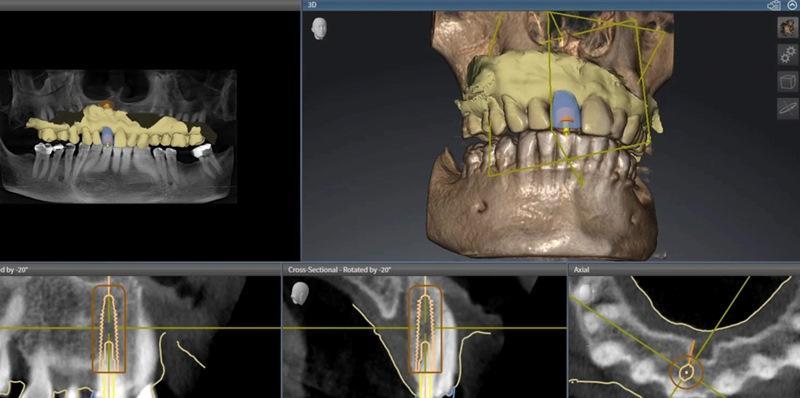

Данные КЛКТ и интраорального сканирования импортированы в программные продукты inLab и SICAT (Dentsply Sirona) для планирования установки имплантата. В ПО на виртуальную дугу был размещен коронковый отдел зуба 1.1 для протез-ориентированного позиционирования имплантата с учетом предполагаемого расположения окончательной реставрации и имеющейся анатомии (Фото 4). Виртуально задана позиция имплантата под размер 4,2×13 мм (Spiral SB/LA Implant, Ritter Implants). В ПО спроектирован хирургический стент (Фото 5). Хирургический шаблон фрезерован из прозрачного полиметилметакрилата (PMMA) на установке inLab MC X5 (Dentsply Sirona). Ретейнер Essix изготовлен по модели, полученной с 3D-печатной цифровой восковой модели, выполненной на предыдущем приеме.

Фото 4. Виртуальное планирование установки имплантата (нижние изображения) и проектирование виртуальной реставрации (верхние два изображения).